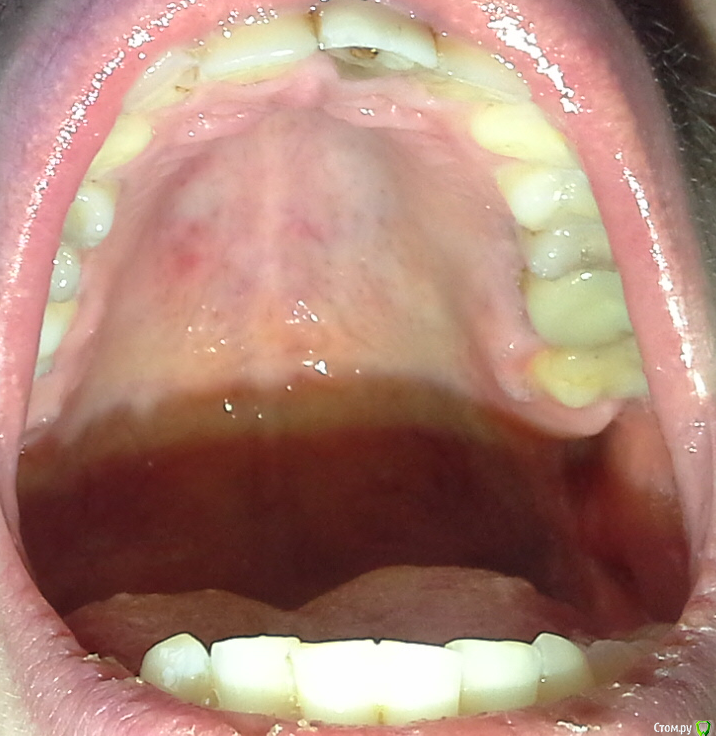

gekelbery Опубликовано 7 февраля, 2016 Поделиться Опубликовано 7 февраля, 2016 (изменено) Долгое время болит нёбо,на общем фоне выделяется белое пятно на слизистой, курю. Есть что-то подозрительное? http://s019.radikal.ru/i609/1602/60/ea6a70def04at.jpg Изменено 7 февраля, 2016 пользователем gekelbery Ссылка на комментарий

gekelbery Опубликовано 7 февраля, 2016 Автор Поделиться Опубликовано 7 февраля, 2016 около полугода Ссылка на комментарий

gekelbery Опубликовано 7 февраля, 2016 Автор Поделиться Опубликовано 7 февраля, 2016 (изменено) Rg есть?нету, нужно сделать какие-то обследования? Ко врачу не обращался, боль то появляется, то пропадает Изменено 7 февраля, 2016 пользователем gekelbery Ссылка на комментарий